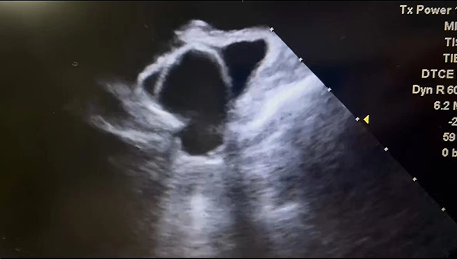

此例手术由韩稳琦博士和酉鹏华博士通过ICE指导下进行,通过ICE精准构建心脏模型、直视下穿刺房间隔,结合三维标测系统,精准、高效地完成双侧肺静脉隔离。后通过ICE及左心耳造影评估左心耳特征为下缘短,上缘折角大的短颈鸡翅型心耳,利用12F导引系统鞘管和猪尾导管在DSA肝位下同时造影,测量左心耳开口25.12mm,最大可用锚定区深度19.71mm,最终选择31mm规格watchman FLX封堵器的植入。ICE从不同角度检查即将释放的WATCHMAN FLX左心耳封堵器,观察封堵器位置、露肩、残余分流和压缩比情况,明确封堵器位置合理,无明显露肩,完全封堵无残余分流,封堵器位置良好。随后在ICE下观察及DSA透视下作牵拉试验,直到最后一次牵拉与前一次牵拉比较无位置改变,压缩比无明显变化,符合封堵器释放的“PASS”原则后完全释放封堵器。

图3 术后ICE观察测量Watchman FLX封堵器位置